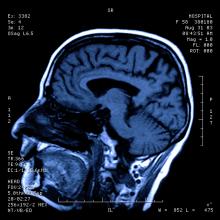

The first patient has been treated in the Boston Scientific Corporation ZERO AF clinical trial to evaluate the safety and effectiveness of the Blazer open-irrigated temperature ablation Catheter in patients with symptomatic, drug refractory paroxysmal atrial fibrillation. This international, multi-center study will include up to 33 sites in the United States, Europe and Asia-Pacific, and as many as 472 patients. The results of the ZERO AF trial are expected to be used to support a U.S. Food and Drug Administration (FDA) regulatory submission for a paroxysmal atrial fibrillation indication.